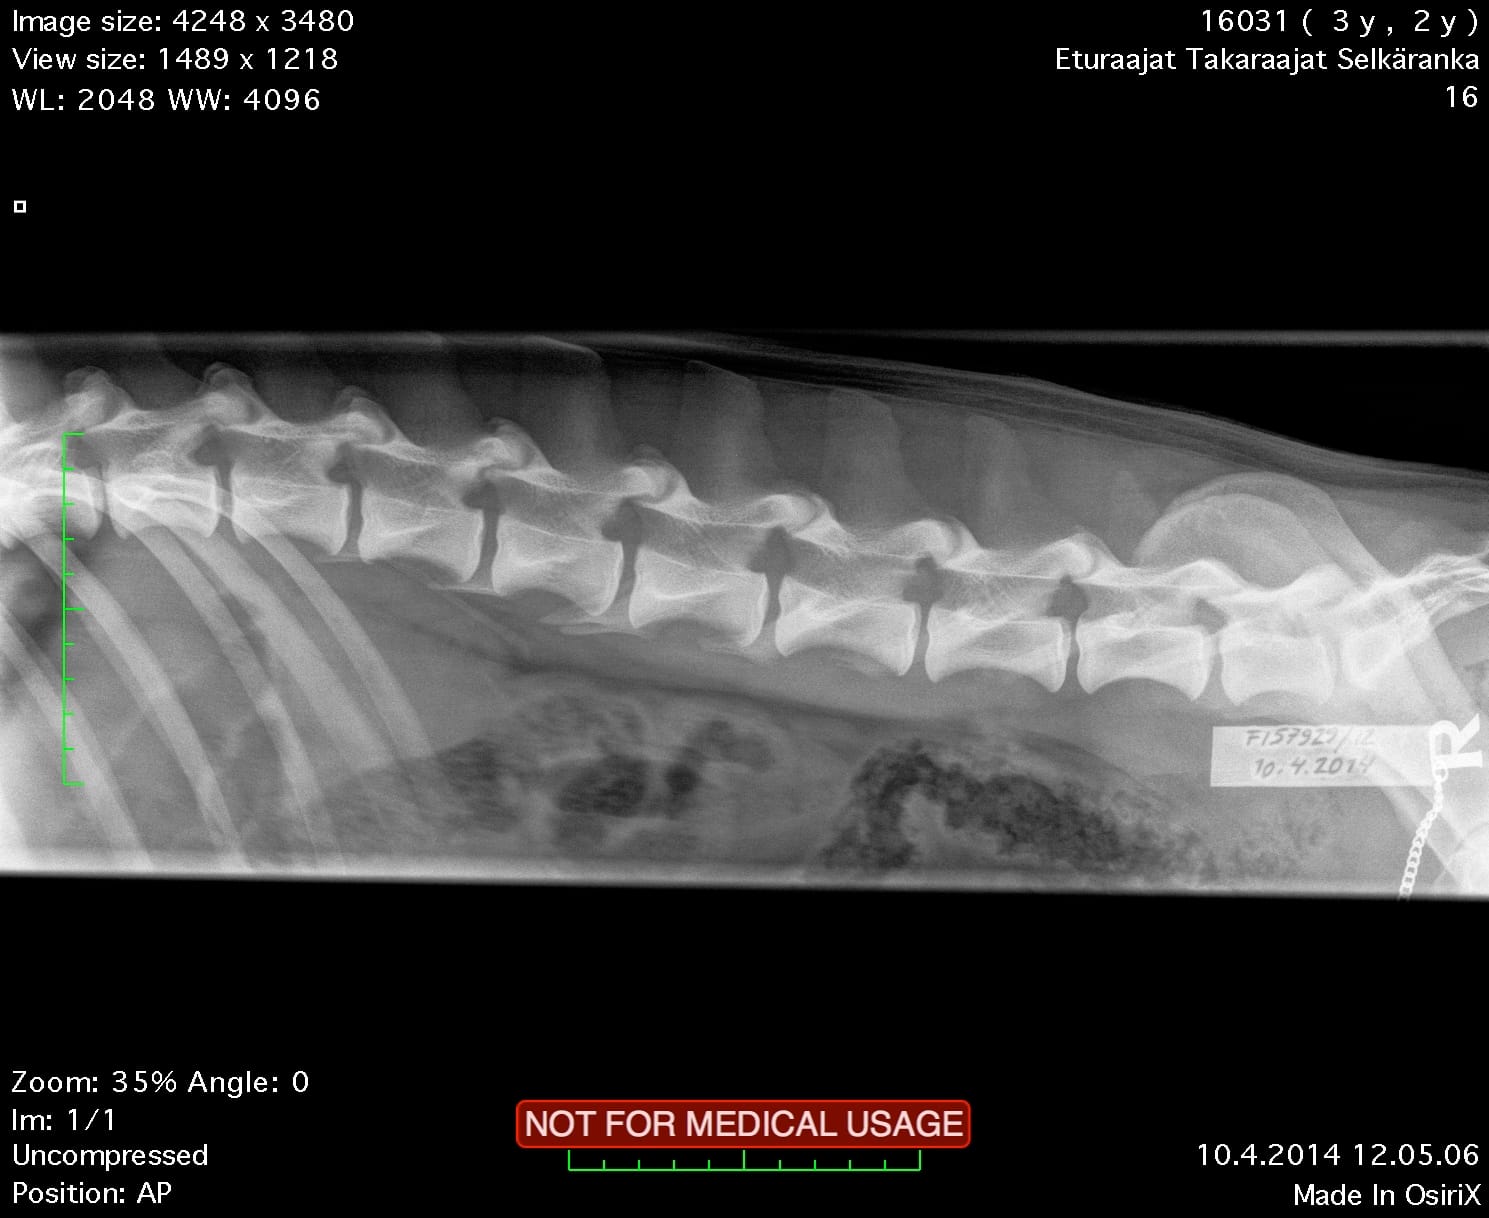

| Spine: | SP0, LTV4 (8 lumbosacral vertebrae) | |